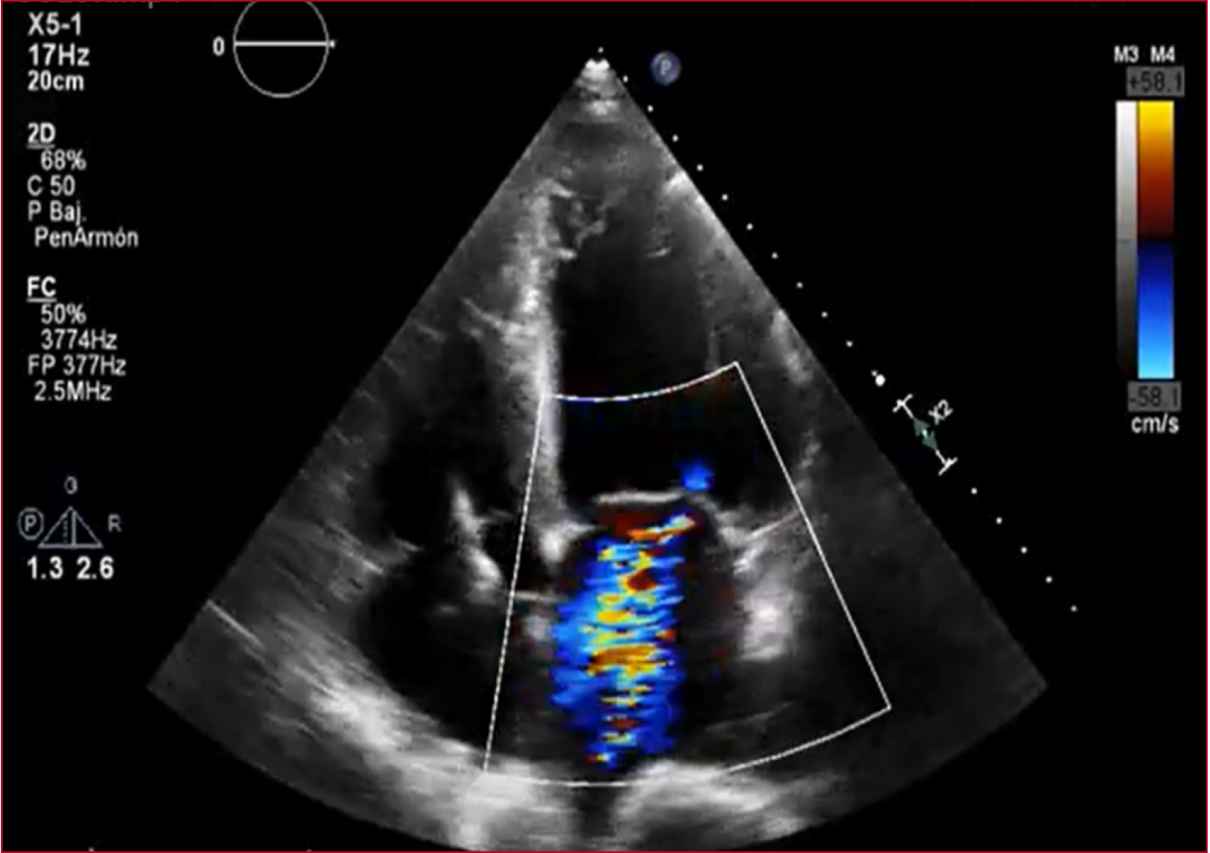

La ecocardioscopia reveló una dilatación

severa de la aurícula izquierda y ligera de la aurícula derecha, un ventrículo

izquierdo severamente dilatado con disfunción sistólica moderada (FEVI 38%, SLG

-13%), un ventrículo derecho ligeramente dilatado con disfunción sistólica

moderada, una prótesis valvular aórtica con signos de estenosis con parámetros

en el límite de la severidad; insuficiencia aórtica ligera, insuficiencia

mitral moderada por dilatación del anillo y tenting predominante del

velo posterior e hipertensión pulmonar severa (Figura 1).

Figura 1. Ecocardioscopia transtorácica en Doppler color, 4 cámaras. Se observa insuficiencia mitral moderada.